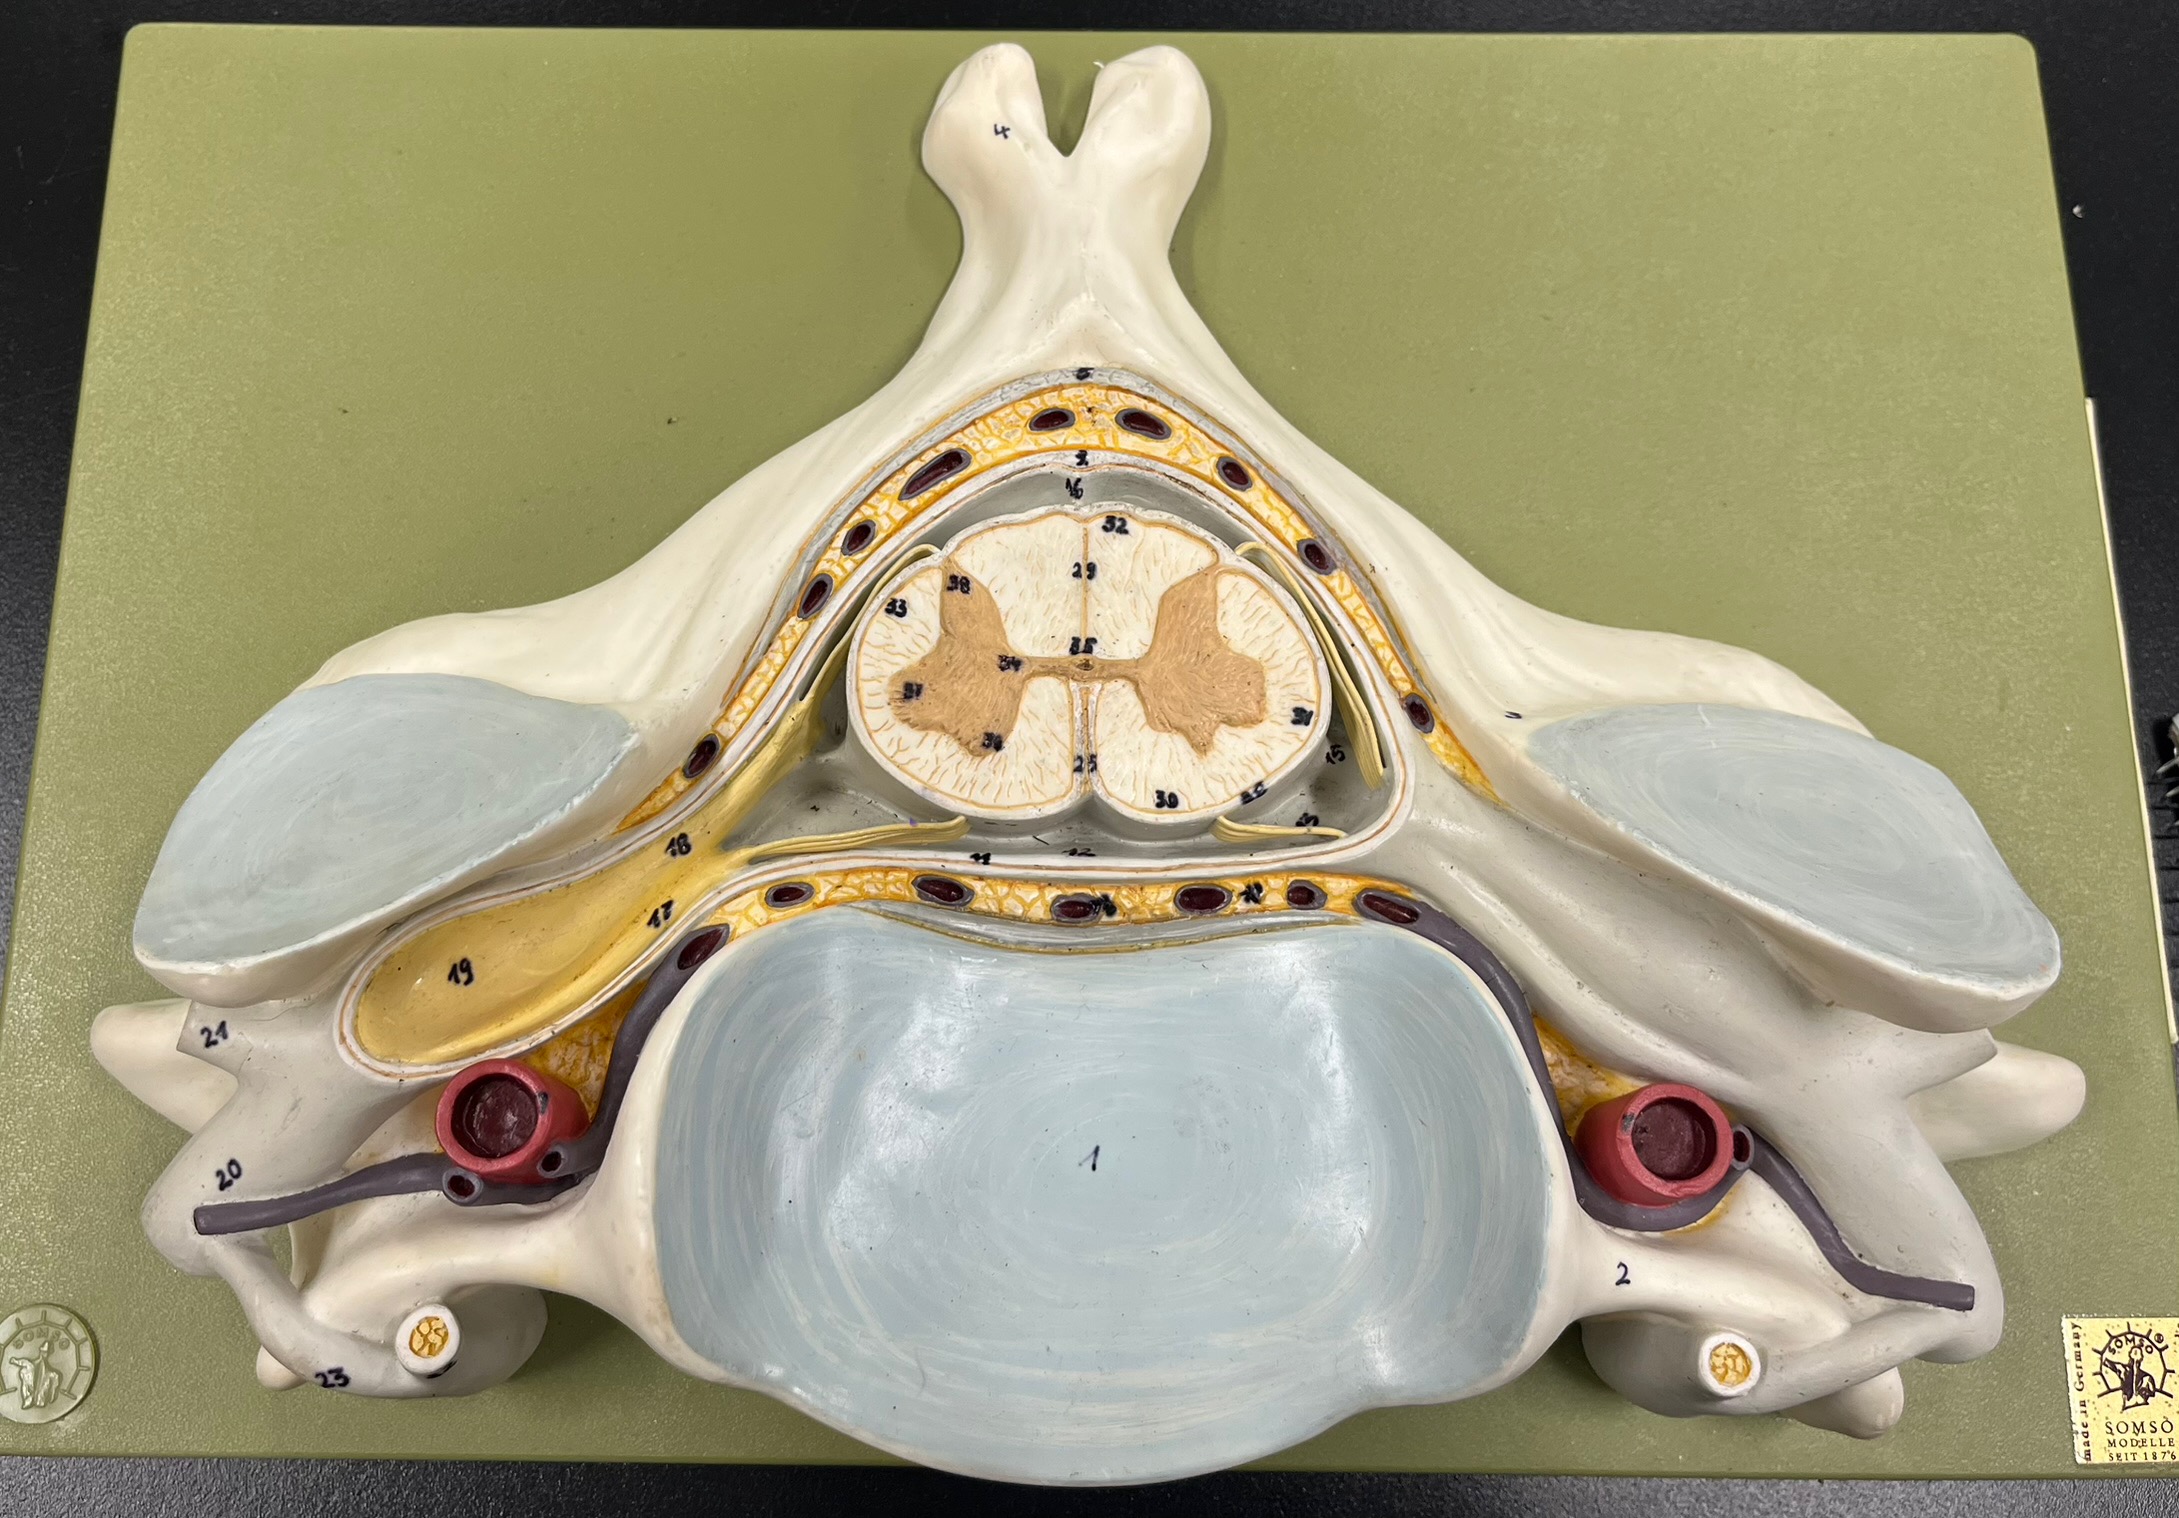

epidural space

dura mater

subdural space

arachnoid mater

subarachnoid space

pia mater

denticulate ligaments

What is the groove here?

anterior median fissure

posterior median sulcus

posterior (dorsal) horn

posterior (dorsal) horn; R—>L

anterior (ventral) horn

lateral horn (selected models)

gray commissure

central canal

anterior column

lateral column

posterior column

white commissure

posterior (dorsal) root ganglion

What is the bulb here?

posterior (dorsal) root ganglion

posterior (dorsal) root

posterior (dorsal) root

anterior (ventral) root

anterior (ventral) root

dorsal ramus

dorsal ramus

ventral ramus

ventral ramus

rami communicantes

rami communicantes

sympathetic chain ganglia

sympathetic chain ganglia